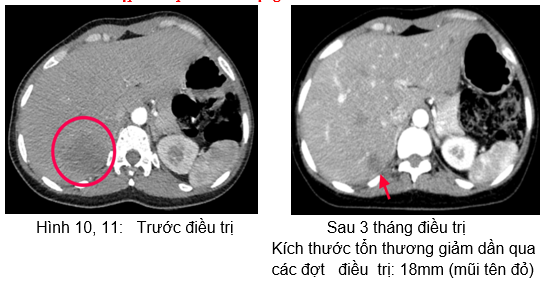

Hình 5: Tổn thương gan trước điều trị: khối giảm tỷ trọng ở hạ phân thùy S7, kích thước 37x45mm, ngấm thuốc kém sau tiêm.

 Chụp cắt lớp vi tính ổ bụng:

Hình 12: Hình  ảnh CT ổ bụng sau 6 tháng điều trị: Khối nhu mô gan hạ phân thùy S7 giảm tỷ trọng, ngấm thuốc kém sau tiêm,

Kích thước tổn thương giảm dần qua  các đợt   điều  trị: và 15mm (mũi tên xanh).

Như vậy, bệnh nhân đáp ứng khá tốt với Erlotinib: chất chỉ điểm khối u, kích thước tổn thương phổi, tổn thương gan có xu hướng giảm dần.